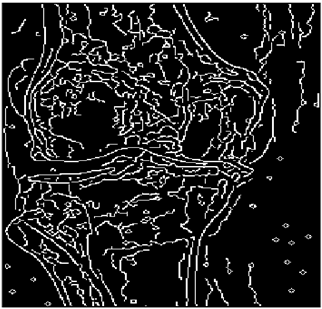

Table 5. X-ray Images.

X-ray 1X-ray 2X-ray 3X-ray 4X-ray 5

Mathematics 10 02421 i004 Mathematics 10 02421 i005 Mathematics 10 02421 i006 Mathematics 10 02421 i007 Mathematics 10 02421 i008

For the purpose of simulation, we consider two sets of images: (1) three images from MATLAB repository (Table 4) and (2) five X-ray images available online (Table 5).